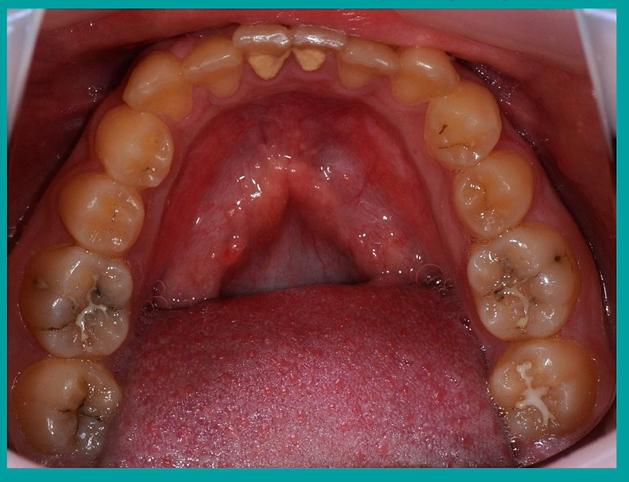

spot the caries

lower right and left second molars

are they the same colour? - the lower right has a fissure sealant

black one indicates staining and possible caries